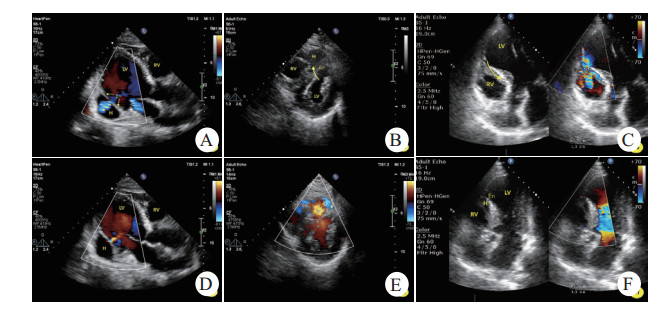

1.1 病例1男,69岁,胸痛6 d,急诊查体发现心尖区Ⅲ/6级收缩期杂音,心电图提示“下壁、后壁导联ST段上抬”,当日床旁超声心动图提示“左室下后壁运动异常,心包腔少-中量积液”,未发现穿孔或夹层。收入CCU后杂音持续存在,次日申请超声会诊,提示“左室后壁中间段心肌夹层(夹层瘤大小1.8 cm×1.6 cm)”(见图 1-A, B),同日左心声学造影证实上述诊断。临床给予药物治疗。住院第13天复查床边超声发现夹层瘤较前增大(3.3 cm×2.8 cm);第24天左心声学造影发现夹层瘤处心外膜断裂,假性室壁瘤形成,心包积液增多。会诊无外科手术指征,介入亦对预后改善不详,继续以内科保守治疗为宜。30 d病情好转出院。6个月后门诊复查超声提示“左室下后壁心肌夹层假腔内血栓形成(4.4 cm×3.4 cm)”。

| A.左室后壁心肌内夹层血肿,内膜分离清晰可见,而心外膜完整,收缩期左室血流通过交通孔进入血肿内;B.舒张期血流再经交通孔返回左室;C.心尖肌层内血肿,内膜呈不规则断裂;D.左室血流涌入血肿并与右室交通,心肌交通路径非同水平;E.室间隔内匍匐状夹层瘤,左室面见断裂的心内膜,收缩期左室血流进入夹层瘤并再次破入右室;F.舒张期夹层瘤腔隙变小。LV.左室,RV.右室,H.夹层血肿/夹层瘤,En.心内膜 图 1 不同部位心肌夹层超声表现 |

男,69岁,胸痛7 d,急诊查体发现胸骨左缘第4~5肋间4/6级连续性杂音,心电图提示“V1~4导联ST段抬高”,床边超声心动图提示“前间隔、左室前壁运动异常,左室心尖夹层瘤(2.5 cm×1.4 cm)形成并室间隔穿孔(非夹层水平)”(见图 1-C, D),临床治疗上给予药物治疗为主。1周后全麻下行室间隔封堵术,封堵未成功,术后患者血压进行性下降,一周后出现心源性休克,抢救无效死亡。

1.3 病例3男,70岁,胸痛2 d,急诊查体发现胸骨左缘第2肋间3~4级性质粗糙的收缩期杂音,心电图提示“前间壁相关导联ST段升高”,床旁超声心动图提示“前间隔、左室前壁运动异常并心尖部室壁瘤形成,室间隔穿孔并夹层,心包腔少量积液”(见图 1-E, F)。该患者放弃治疗。